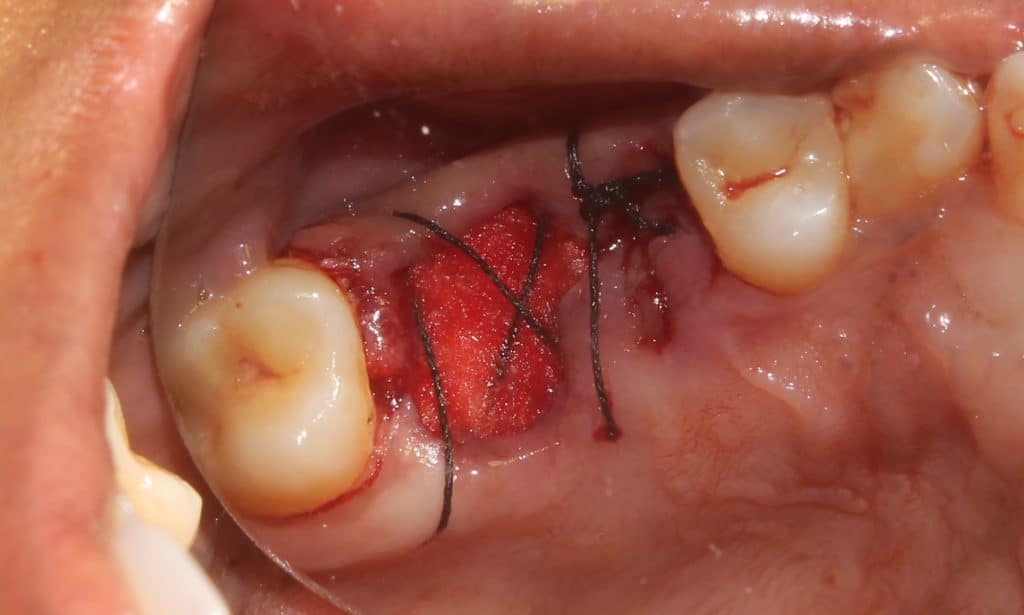

collagen sponge and figure of 8 suturing to protect the blood clot..